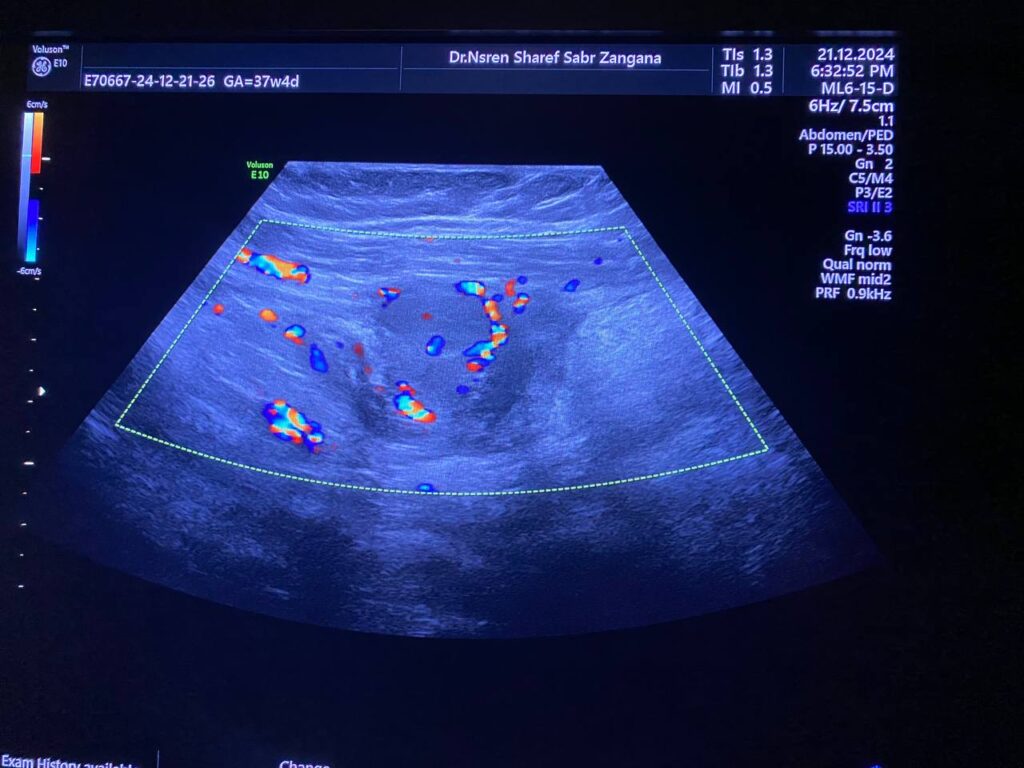

· Left ovary , normal in size , no dominate follicle , with presence of heterogenous vascular solid mass, contain calcification size about 44x30mm with indistinct margin, vascular on color doppler, score 3-4 located just the lateral to the left ovary , with invasion of the adjacent peritoneal & muscular layer ( left rectus abdominis muscle) , mostly suspicious mass , its invasion to the left ovary cannot be excluded , picture could be Desmoid tumor ? peritoneal tumor > , for further study please . no suspicious lymph node seen

- Evidence of 6 X 4 X 3cm multilocular mass in Lt lower abdomen, arises from Lt adnexa “attached to uterus and Lt ovary”, invades posterior aspect of Lt rectus muscle, in contact with Lt inferior epigastric artery, also in contact with loop of small intestine with no frank invasion, this mass has surrounding fat stranding, which makes it possible to be infection like tubo-ovarian abscess, although malignancy can not be excluded, lab studies and MRI is suggested for further evaluation please.